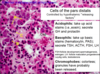

pancreas

How to differentiate zones of the cortex of the adrenal gland?

The zona fasiculata is much more pale staining and you see empty space here. The zona fasciculata cells have lipid components and this is extracted during staining. This is why it looks white. But these cells are also much more puffy looking compared to the cells around them. And finally over here is the zona reticularis.

In the zona fasciculata the cells are in straight cords, in the reticularis you can see much more branching rather than straight lines.